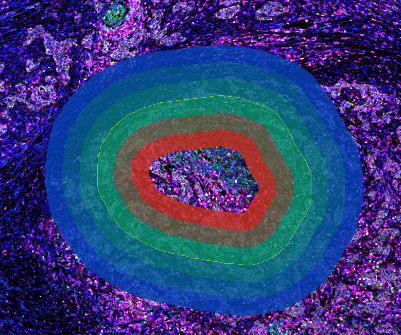

TMA分割模块,支持多样本来源组织芯片图像研究

TMA分割